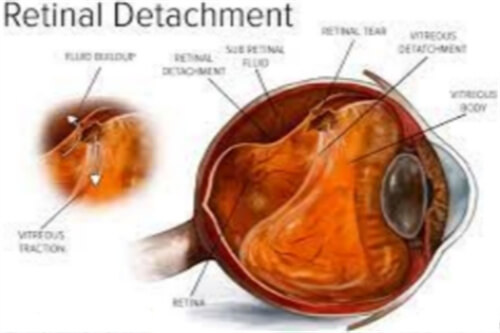

突发预案:10%患者可能出现继发青光眼,应急处理费用约2000元。视网膜水肿需注射雷珠单抗,单针费用5000-8000元。

在显微镜下,医生用精细工具(如视网膜钩或镊子)小心抓住并剥离前膜,尽量减少对视网膜的损伤。

剥除后,详细检查视网膜表面是否有残留膜,并清理干净。然后,向眼内注入平衡盐溶液维持眼球形状,闭合切口。

术后,患者需使用抗生素和抵***症滴眼液预防感染,并定期复查以确保改善进程。